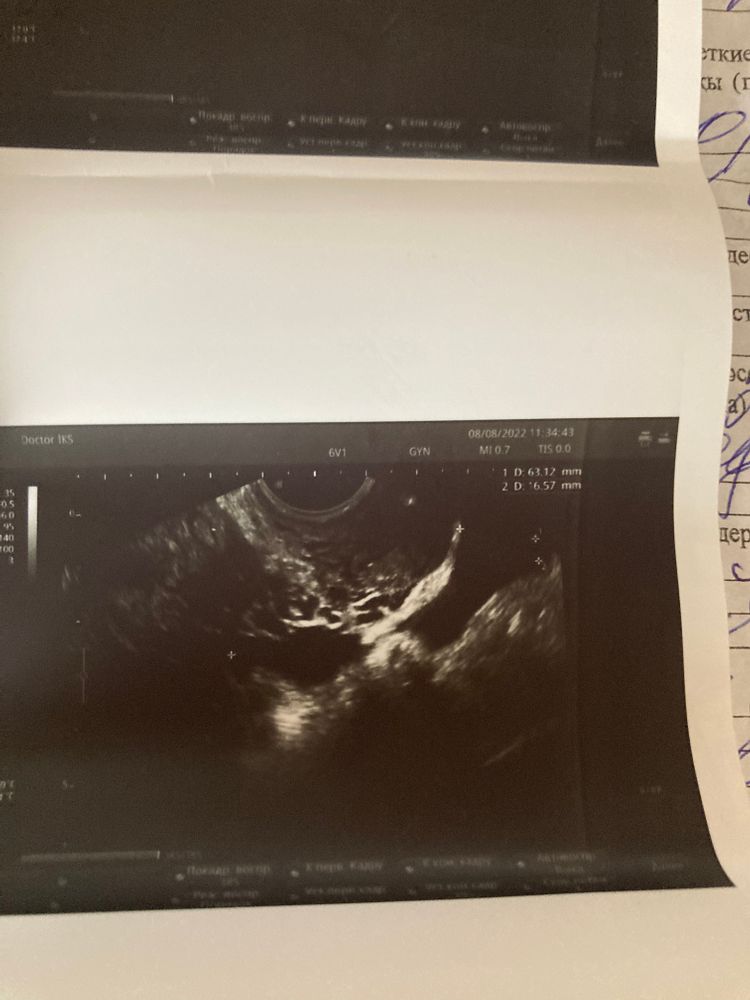

ФолликулометрияДевочки кто понимает узи снимки есть тут Желтое тело?

Последний снимок сказала жидкость за маткой